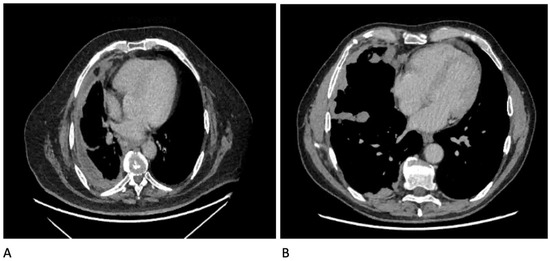

13. Ultrasound

14. CT